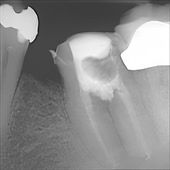

Hier sehen Sie den gleichen Zahn einige Wochen später nach erfolgreicher Aufbereitung der Nervenkanäle, sorgfältiger Desinfektion des Inneren der Wurzeln, Ausheilung der Knochenentzündung und Abheilung der Fistel nach erfolgreicher Wurzelfüllung bis zu den Wurzelspitzen. Der dunkle Bereich der Knochenentzündung aus dem ersten Bild ist verschwunden. Der Zahn ist wieder völlig fest. Man sieht aber, dass Wurzelfüllungsmaterial aus dem Zahn zwischen die Wurzeln gelangt ist. Das ist ein deutliches Zeichen dafür, dass sogar der Zahnboden bereits zerstört war.